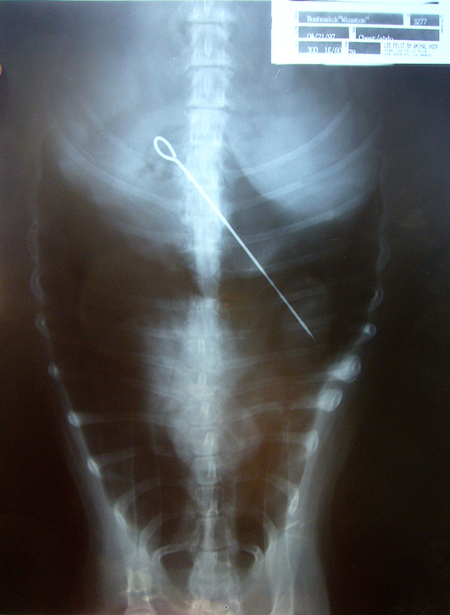

Winston had a good life even through the eating of a turkey skewer. He found his way into the garbage one Thanksgiving and managed to eat the skewer. The vet was sure somebody was playing a trick on him when he saw the X-ray. So at 14, Winston went in for surgery to remove his skewer. He survived this, then managed to injure an eye fighting with the dog next door. Then he needed to have his eye removed. In the end he was a tough little pirate dog, with a patch, and big scar.